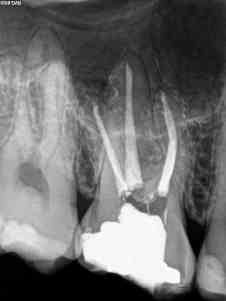

A)  Nos encontramos con un 1.7, con una necrosis pulpar con afectación periapical.

A)